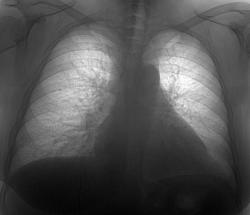

Добрый день коллеги! Сегодня проглядывал снимочки легких, по просьбе своей коллеги, с целью исключения метастазов и увидел  представленную картину. Пациентка 50 лет, лежит  в стационаре с диагнозом: Злокачественное новообразование яичника? Мts в надключичные лимфатические узлы. Мысли сразу про лимфогенные метастазы,  поглядел сразу в архиве ФЛГ от 11.08.09г. два первых снимка, два последних сегоднишним днем. Ваше мнение?

Два последних снимочка это сегоднишние цыфровые рентгенограммы, КТ-у нас пока вышло из строя. По УЗИ находят образование в почке и яичнике.

Я бы не рискнул "увидеть" на представленных Вами снимках лимфогенные метастазы (не смотря на анамнез). На мой взгляд, динамика по снимкам несущественна, да и та связана с застойными изменениями в легких. А на фоне застоя лимфогенные метастазы по рентгенограмме отдифференцировать очень трудно.

В том то и дело уважаемый Alex застойные изменения в МКК, минимальные, а картина похожа на лимфастаз.

Поддерживаю пост Alex, в той части, что симптоматика по флюорограмме за лимфогенные  метастазы неубедительная(возможно на КТ их будет видно). Усиление лёгочного рисунка, вероятно не связано с застойными изменениями( нет признаков гипертензии вен верних долей( симптома "оленьих рогов"), который рассматриваеться, как I стадия левожелудочковой недостаточности).